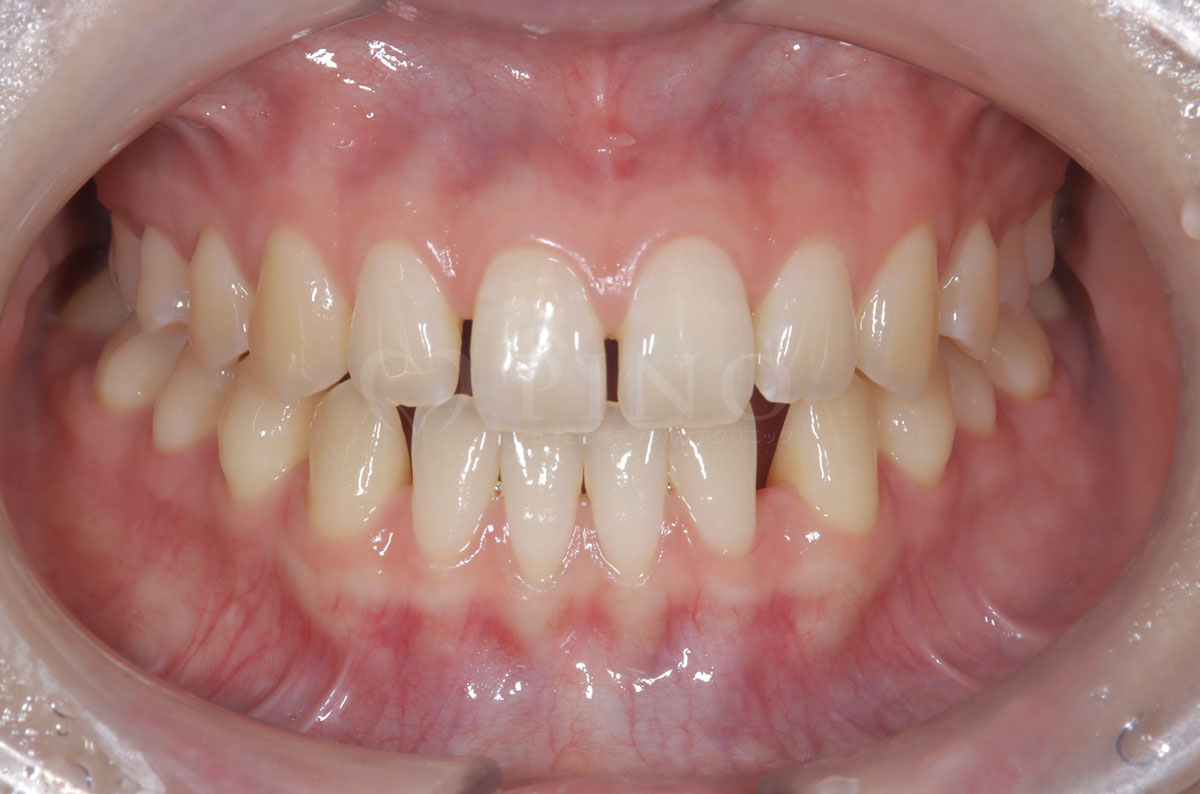

症例4:噛み合わせが深く、下の歯が見えないのが気になる(10代女性)

主訴 噛み合わせが深い、下の歯が見えない 診断名 過蓋咬合(かがいこうごう) 治療方法 マウスピース全顎矯正 抜歯 なし オルソパルス なし 治療期間 1年1ヶ月 費用 746,000円 副作用・注意点 矯正後の後戻りを防ぐためリテーナーの使用が必要となる -